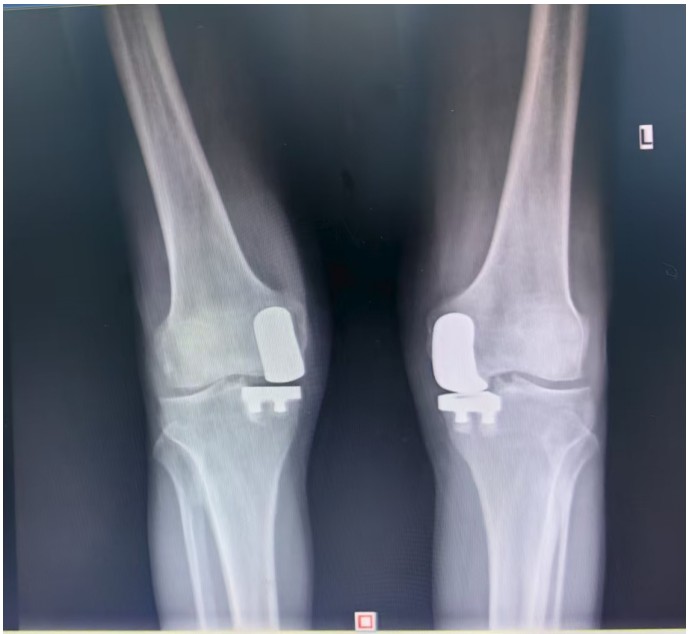

據(jù)了解,患者1年前無明顯誘因出現(xiàn)雙膝關(guān)節(jié)疼痛,以右側(cè)膝關(guān)節(jié)為主,近5個月來雙膝關(guān)節(jié)疼痛明顯加重,不但日常行走困難,生活質(zhì)量更是受到極大影響。經(jīng)多家醫(yī)院治療效果均不理想,了解到衡陽市中心醫(yī)院關(guān)節(jié)外科在關(guān)節(jié)置換領(lǐng)域擁有豐富的臨床經(jīng)驗和良好的患者口碑,毅然決定赴衡求醫(yī)。醫(yī)生發(fā)現(xiàn)患者雙膝關(guān)節(jié)已有內(nèi)翻畸形,關(guān)節(jié)內(nèi)側(cè)骨性膨大,X線提示雙膝退行性病變,雙膝內(nèi)側(cè)間隙明顯狹窄,手術(shù)為最佳治療方式。為了達到根治目的,羅湘平主任醫(yī)師、彭健副主任醫(yī)師為患者進行了詳細查體及綜合評估,術(shù)前組織開展多學(xué)科討論(MDT)。考慮到易叔叔的膝關(guān)節(jié)骨關(guān)節(jié)炎僅局限于內(nèi)側(cè),外側(cè)間室軟骨良好,若采用全膝關(guān)節(jié)置換術(shù)會將失去正常關(guān)節(jié)間室的軟骨與韌帶,創(chuàng)傷較大,便為其制定了右膝關(guān)節(jié)單髁置換手術(shù)治療方案。在充分完善術(shù)前準備后,羅湘平主任、彭健副主任醫(yī)師團隊為患者實施了右側(cè)膝關(guān)節(jié)單髁置換術(shù)。手術(shù)過程順利,團隊應(yīng)用微創(chuàng)術(shù)式(MIS)及“精準間隙平衡技術(shù)”,最大程度減少了手術(shù)創(chuàng)傷,為術(shù)后快速康復(fù)奠定了堅實基礎(chǔ),術(shù)后第二天即可借助助行器下地活動。6天后團隊順利為患者實施了左側(cè)膝關(guān)節(jié)單髁置換手術(shù)。目前,易叔叔在關(guān)節(jié)外科醫(yī)護團隊的精心指導(dǎo)和康復(fù)治療下,恢復(fù)情況良好,雙側(cè)膝關(guān)節(jié)活動度輕松達到90°,膝關(guān)節(jié)功能顯著改善,能夠獨立下地行走,對手術(shù)效果非常滿意,已于9月10日順利出院。

羅湘平主任介紹,膝單髁置換術(shù)是針對膝關(guān)節(jié)單側(cè)間室病變的微創(chuàng)手術(shù),該術(shù)式通過置換單側(cè)股骨或脛骨受損軟骨表面,保留交叉韌帶及正常骨質(zhì)結(jié)構(gòu),因創(chuàng)傷小、恢復(fù)快被稱為膝關(guān)節(jié)置換中的“補牙”技術(shù),適用于單間室骨關(guān)節(jié)炎且韌帶功能完整的患者。膝關(guān)節(jié)單髁置換為特定的膝關(guān)節(jié)疾病患者提供了一種較為理想的治療選擇,它以較小的手術(shù)創(chuàng)傷、良好的術(shù)后功能恢復(fù)效果,幫助患者緩解疼痛,恢復(fù)正常的生活和活動能力。